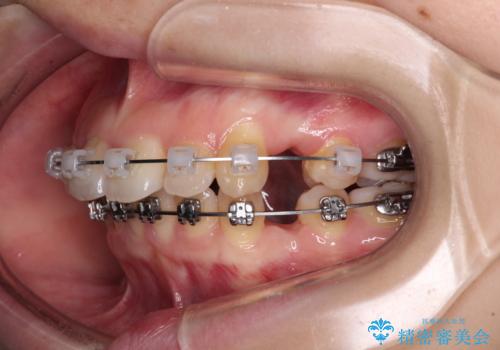

- メタルブラケット

舌の突出癖があり、前歯の移動量も多くなるため、治療期間は長くなると予想されましたが、13ヶ月という予定の半分程度の期間で終えることができました。

※写真にある上顎装置はメタルブラケットではありません。メーカー在庫都合などにより別の装置を使用しております。